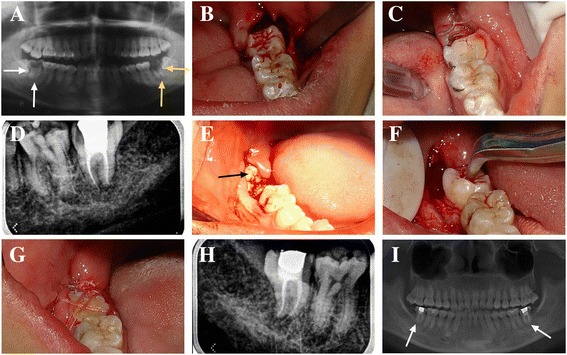

Fig. 1.

Course of treatment and long-term follow-up in a 24-year-old patient who had 2 third molars transplanted. The #38 tooth replaced the #37 tooth, and the #48 tooth replaced the #47 tooth. a A panoramic radiograph revealed severe caries of the left and right mandibular second molars (#37, #47). Radiolucent areas were visible at the apices of the #37 and the #47 teeth. Neither could be restored, and both were extracted. b The #38 tooth was transplanted into the #37 position after being rotated 180°. c The #38 tooth was fixed with wire after occlusal adjustment. d An intraoral radiograph of the #38 tooth immediately after endodontic treatment 4 weeks after transplantation. e An intraoral photograph of the #48 tooth before transplantation. f The #48 tooth was transplanted into the #47 position after being rotated 180°. g The #48 tooth was fixed via suturing because the #48 tooth extended too far. After occlusal adjustment, the edge of the #48 tooth was at the level of the gingiva, and it was difficult to fix with wire. h An intraoral radiograph of the #48 tooth immediately after endodontic treatment 4 weeks after transplantation. i Panoramic radiograph after 7 years of follow-up. The radiolucent areas at the apices of the #38 and the #48 teeth have disappeared